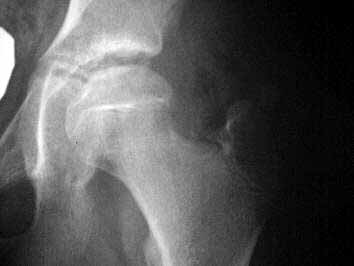

I appreciate some advise on this case. 11 y o girl doing high performance gymnastics in USA. On a fall over the left foot have done a forced medial rotation of the left hip, feeling pain on the buttock and thigh. Stopped the activity for a week and returning to sport, didn't reach the same performance, complaining of pain and limping when she make efforts, this lead her to abandon gymnastics. It have been diagnosed as Perthes disease. I am attaching xr and relevant mri. Your opinion is welcomed.

But, her femoral head is still spherical, it looks to be about the same size as the other head, and her joint space is preserved. Those are all good things.

The eleven year old female gymnast presents with an xray image of the left hip which looks more benign than the MRI which shows coxa plana with resorption of bone in a large area of the femoral capital epiphysis and widening of the femoral neck. These changes and the patient's gender and age mean a poor prognosis for Legg-Perthes disease which I believe this case represents. Was the MRI done somewhat later in the course of time than the X-rays? I could not make out dates on the images. There is one feature of the MRI which might be favorable: the enlarging femoral head does not seem to extrude far beyond the edge of the acetabulum as marked by the thorn sign. This indicates that satisfactory containment might still be obtained by upper femoral varus-producing osteotomy. I would confirm this possiblity by a dynamic arthrogram at the time of surgery; if the femoral head centers well enough with up to 30 degrees abduction for the edge of the acetabulum to drop down around it, the upper femoral osteotomy might bring a good short term outcome. Otherwise, I might consider a double osteomy: upper femoral and innominate. Left alone, the hip will probably go on to hinge-abduction with attendant pain and stiffness.

Regarding this case, I am grateful by your opinion. After careful analysis of the history and films, I am convinced that this is not a Perthes disease. In fact, on this case there are a violent traumatic event that have provoked the lesion, which is not compatible with Perthes. On the other hand, the MRI pattern is not what I am used to seeing. The patient presents a voluminous joint effusion and a image of anterior impaction of the femoral head with a thin layer of subchondral necrosis under the compacted zone (jb02).

In Perthes, the necrosed zone generally includes a deep thickness of the epiphysis. On the other hand, it doesn't seem to have articular cartilage thickening, one of the 1st signs of Perthes. Finally on the MRI one can see a rupture of the lateral rotator muscles, including gemelli, obturators and quadratus, with abundant extra-articular effusion, which never happens in Perthes disease and shows the violence of the accident (jb01).